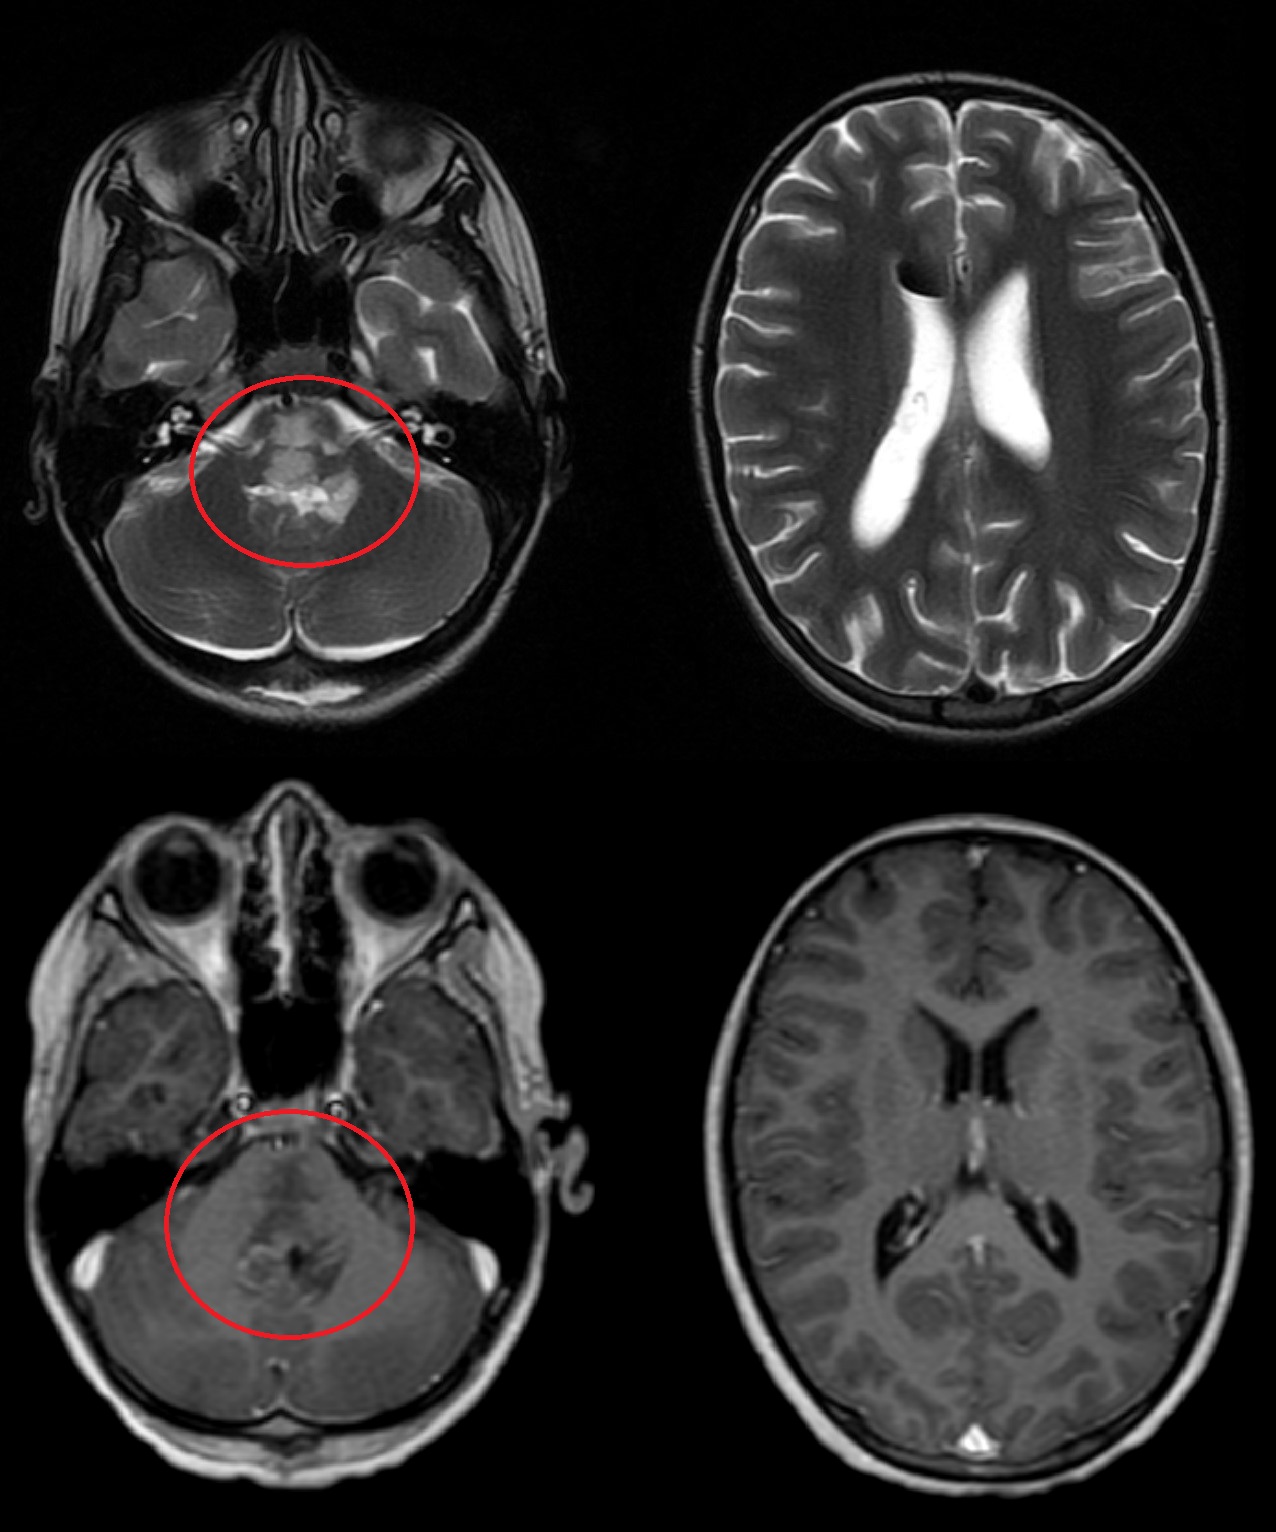

Результаты. У 19 пациентов (50 % от 38 прошедших биопсию) по данным иммуногистохимического анализа послеоперационного материала была выявлена мутация К27М в гене H3F3A. У 6 (15 %) пациентов из 38 МРТ в сроки от 2 до 5 мес (медиана – 4,5 мес) после окончания лучевой терапии выявлено нехарактерное прогрессирование ДСГ в виде метастазирования по желудочковой системе головного мозга. У остальных пациентов когорты исследования, не проходивших процедуру биопсии, подобный характер прогрессирования не наблюдался (p<0,002): у них, как правило, отмечался продолженный рост опухоли (n=96), у 4 больных диагностировано лептоменингеальное метастазирование по спинному мозгу.

Заключение. Нами выявлены случаи нетипичного прогрессирования ДСГ в виде метастазирования по желудочковой системе у детей после открытой биопсии опухоли. Есть основания полагать, что биопсия могла способствовать диссеминации ДСГ по ликворным пространствам. Необходим поиск альтернативных методов оценки молекулярно-генетических характеристик ДСГ.